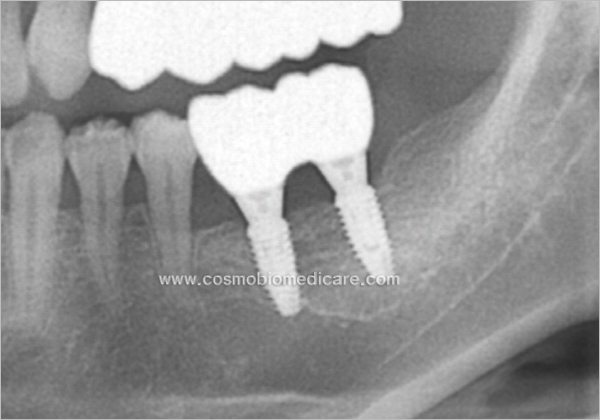

Clinical Cases

• Case1

• Case2

• Case3

• Case4

• Case5

• Case6

• Case7

• Case8

• Case9

• Case10